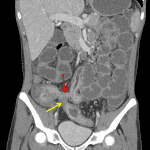

- Extensive mural thickening, submucosal edema, and mucosal hyperenhancement involving the terminal ileum

- Additional segmental mural thickening and mucosal hyperenhancement extending from the descending colon through the rectum

- Peripherally-enhancing fluid collection adjacent to the cecum measuring 1.1 x 1 x 0.9 cm

- Enterocolonic fistula bridging the terminal ileum and sigmoid colon and adjacent enteroenteric fistula

- Small volume abdominopelvic ascites

- Diffuse mesenteric edema

- Crohn disease with small bowel obstruction, fistulas, and abscesses

Findings concerning for active inflammatory bowel disease (most consistent with Crohn disease) with segmental inflammation of the terminal ileum and distal colon and rectum. Associated upstream small bowel distension, enteroenteric and enterocolonic fistulas, and pericecal and perirectal abscesses.